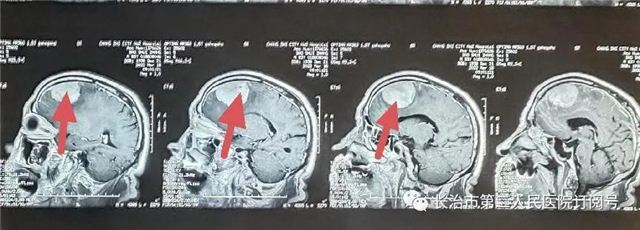

▲核磁检查见小脑幕下肿瘤,强化明显,考虑脑膜瘤。

(红色箭头为肿瘤)

本病例因幕下空间小,肿瘤压迫小脑,紧邻横窦、窦汇、脑干。手术风险高一旦出血,将危及生命。术后复查肿瘤切除干净,瘤腔未见出血。现患者已痊愈出院。